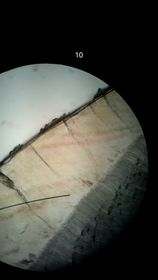

Diente Capa externa, esmalte